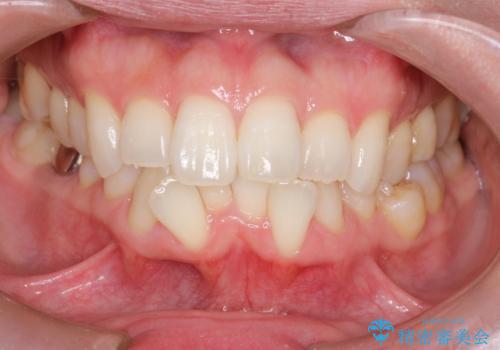

【インビザライン】がたつきをなおしたい

- 上下の前歯の凸凹が気になり、来院されました。

インビザラインで綺麗に仕上がり、満足していただきました。